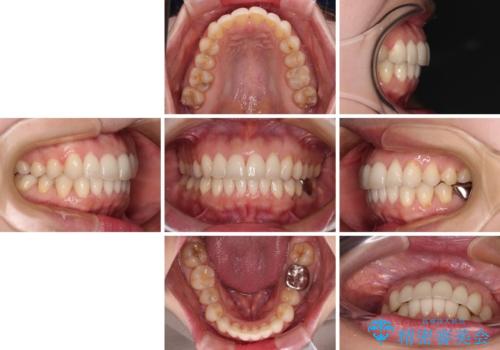

- 上下の前歯のデコボコを気にして来院された患者様です。

妊娠中であり、途中通院が難しくなる可能性があることから、インビザラインによる矯正治療を行うこととしました。

上下顎歯列全体の後方移動とIPR(歯と歯の間を削る)によってデコボコが解消するように設計しました。